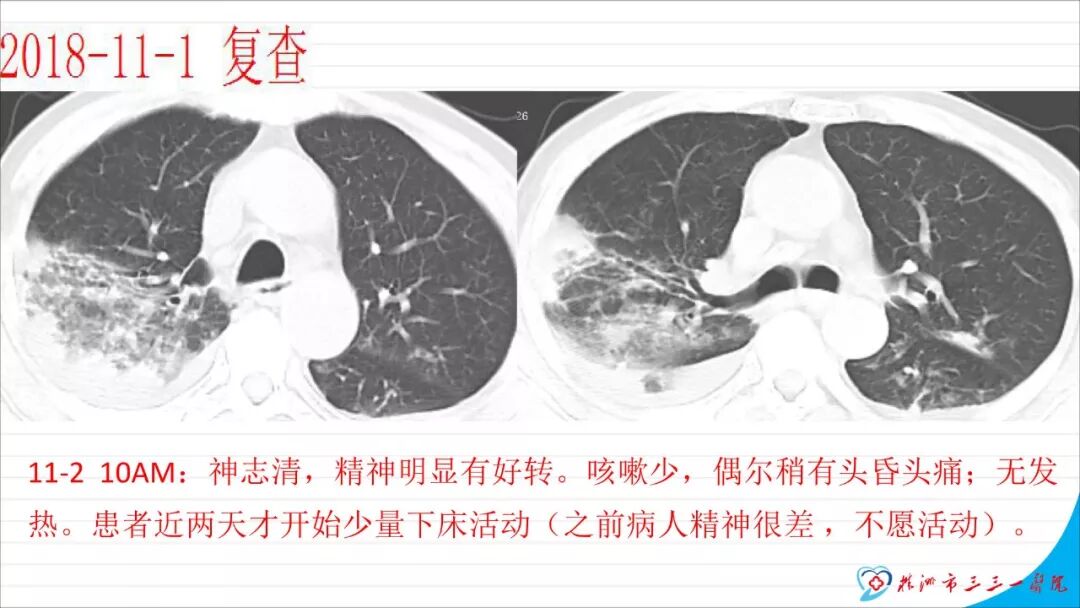

本文以“慢性硬膜下血肿自然演变一例”为题,恰当!因为此例患者系从急性硬膜下血肿自然演变而来。只是长期口服他汀没有起到预防作用。本例患者与其说是阿托伐他汀治疗慢性硬膜下血肿无效,还不如说是阿托伐他汀不能阻止急性硬膜下血肿向慢性硬膜下血肿演变的过程,当然,后续急性血肿变成慢性后,阿托伐他汀似乎也没有发挥治疗作用。需要指出的是,单药阿托伐他汀治疗急性硬膜下血肿并无成功病例报道,但是,本例报道还告诉我们,它还不能阻止急性硬膜下血肿向慢性血肿演变,值得关注。 谈到阿托伐他汀治疗慢性硬膜下血肿,我们是始创者。为此,看到作者似乎有点抱怨的情绪,我得做些解释。我们ATOCH试验,验证的是阿托伐他汀治疗慢性硬膜下血肿比安慰剂能更有效促进血肿吸收,没有发现也没有努力去验证阿托伐他汀治疗慢性硬膜下血肿100%有效,因此发生治疗无效很正常。 保守治疗的始作俑者是英国人,他们1962年就提出地塞米松治疗慢性硬膜下血肿。但是,迄今为止,无论是英国人提出的地塞米松、美国人提出的氨甲环酸或血管紧张素转换酶抑制剂,还是德国人提出的塞來西布,日本人提出的汉药,国内许多单位自行研究提出的血府逐瘀丸,作者单位的“传统”方法红花注射液治疗慢性硬膜下血肿都没有经历严格随机双盲安慰剂对照研究,也从未被大宗病例报道证实过有效。由于未被RCT(随机对照临床试验)证实过,加上一部分慢性硬膜下血肿不必治疗也可以自我吸收(这在我们ATOCH里的安慰剂组中已经观察到,但我们发表论著时没有刻意提出这一点而已),除他汀疗法之外的药物疗法被怀疑是否真具有疗效就顺理成章了。这也是我们的阿托伐他汀治疗慢性硬膜下血肿在保守治疗药物队伍中“一骑绝尘”的理由。后续西南医科大学和香港中文大学还均报道使用阿托伐他汀可以预防慢性硬膜下血肿术后复发。而且,除了有RCT结果支撑其有效性外,安全性明显优于上述各个西药又不像中药或汉药那么含糊,也使得阿托伐他汀成为目前保守治疗慢性硬膜下血肿应用最多的药物。 但毫无疑问,实践中确实屡屡有发现效果不佳的病例。为什么会这样呢?可能有2个理由: 1、确实存在一部分对他汀治疗反应不佳的患者。我们的ATOCH中,阿托伐他汀试验组就有11例患者因无效转去接受手术(对照组则多达23例); 2、ATOCH试验长达8周,有些患者家属和医生都没有耐心等待8周。也就是说,没有等到药物作用显现就转保守治疗为手术治疗。在同样状况下,即使作为发明者,我也不敢“阻扰”患者转手术治疗,因为这意味着风险转嫁。而这种“保守治疗未到时间”(这样提可能不严谨,因为没有规定时间,只有经验时间)就转手术治疗,会增加阿托伐他汀治疗慢性硬膜下血肿的“无效率”。 有鉴于此,我们团队在张建宁教授指导下,从2014年就开始优化阿托伐他汀疗法,本人以此优化的独门方法就治愈了多达200余例各种慢性硬膜下血肿患者。最近,有上海同行私下告诉我,他用类似我的优化方法保守治疗慢性硬膜下血肿多例,还没有失败过。我跟他开玩笑:“那是你治疗的病例还不够多。”实际这不是开玩笑,因为本人有失败经验。目前,我们团队正积极推进ATOCHII试验,就是要证明我们的优化疗法更加有效,期待奉献给世界一个更加好用的治疗慢性硬膜下血肿新方法。 最后需要特别指出的是,慢性硬膜下血肿与急性硬膜下血肿和亚急性硬膜下血肿并非一定有如父如子的“传承”关系。实践中,绝大多数患者都没有急性硬膜下血肿过程,尤其是老年患者第一次查影像学多数就可以确诊慢性硬膜下血肿了,患者之前并没有经历急性硬膜下血肿这种剧烈损伤过程。还有,脑转移癌可以发生类似慢性硬膜下血肿的血肿性病变,先天性蛛网膜囊肿、脑池囊肿术后常见并发症就包括硬膜下血肿。笔者诊疗慢性硬膜下血肿接近300多例,还见过教科书和个案报道没有记载的各种非脑外伤相关慢性硬膜下血肿的病例。相比于脑外伤引起的急性和亚急性硬膜下血肿,慢性硬膜下血肿是处理简单且病情稍显轻微的疾病,但其发生机制却远比急性和亚急性硬膜下血肿更为复杂,值得进一步深入研究。 江荣才 教授 副主任兼NICU主任 天津医科大学总医院神经外科![]()